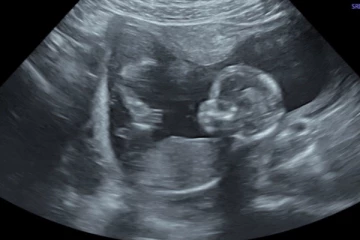

20 ஆண்டுகளுக்கு பின் உருவான கரு! 5 மாதத்தில் மருத்துவர்களுக்கு காத்திருந்த அதிர்ச்சி....பிறகு நடந்த அதிசயம் 4 ஆண்டுகள் முன்